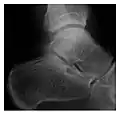

High-energy trauma fractures

Figure 3: A 26-year-old man presenting with wrist pain after being assaulted. (a) Initial anteroposterior radiograph shows a subtle linear lucency within the scaphoid extending to the scaphocapitate articular surface that was overlooked (arrow). (b) Initial "scaphoid" view was negative. (c) Followup anteroposterior radiographs, 12 days later, shows obvious scaphoid fracture (arrows).[1]

Triquetral fracture usually occurs on the dorsal aspect by impingement from the ulnar styloid or avulsion of strong ligamentous attachment. The dorsal avulsion fracture or "chip fracture" appears as a small bony fragment on the dorsal aspect of the triquetrum and is best detected on the lateral view(Figure 4). When radiography is negative in patients with high suspicion of a fracture, both MRI and MDCT will be of value. However, it has been shown that MRI is superior for detecting trabecular fractures in carpal bones.

Figure 4: Dorsal triquetral fracture of the left wrist in a 30-year-old man after a trauma. (a) Anteroposterior radiograph shows a normal appearance. (b) Lateral radiograph of the same wrist demonstrates a chip fracture off the dorsal aspect of the triquetrum (arrow).[1]